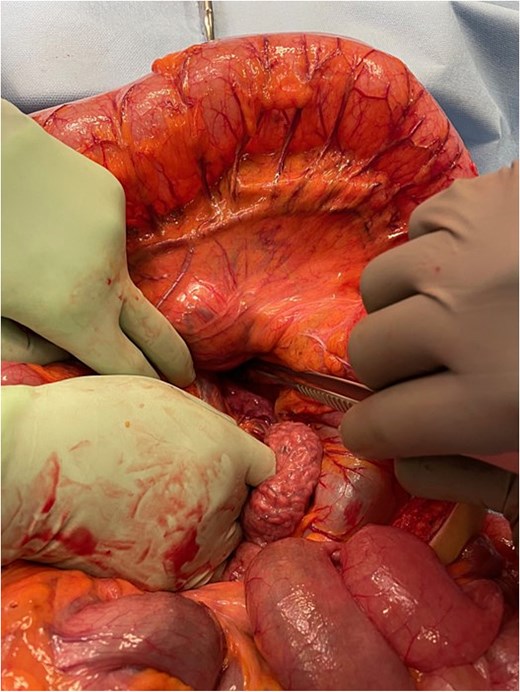

At laparotomy the proximal transverse colon and hepatic flexure were found herniating through the left paraduodenal recess into the lesser sac (Fig. 6). The herniating segment of large bowel was reduced. This segment was healthy and viable. A wide paraduodenal recess, narrow small bowel mesentery and mobile transverse colon exacerbated the herniation tendency into the lesser sac.

Intra-operative image demonstrating mesocolic defect through which the transverse colon had herniated.

The paraduodenal recess was narrowed with three interrupted 2–0 non-absorbable monofilament sutures to the mesenteric peritoneum. It was noted that the base of the small bowel mesentery was short, increasing the risk of total small bowel volvulus. To prevent this, the base of the small bowel mesentery was widened by division of the mesenteric peritoneum. The grossly distended large bowel could not be decompressed into the small bowel and stomach to the nasogastric tube and the ileocaecal valve was found to be competent. An appendicectomy was performed and the large bowel was decompressed with suction via the appendix stump. The appendix stump was then ligated and buried in the caecum with 3–0 absorbably monofilament purse-string suture. Thorough washout of the abdominal cavity was performed and the abdomen closed.